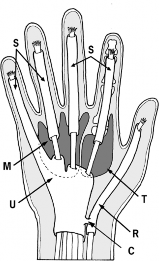

Stability of the thumb MCP joint is paramount for effective key pinch and cylindrical grasp. This stability is conferred by both static and dynamic restraints. The static stabilizers include the proper collateral ligament (PCL), the accessory collateral ligament (ACL), the volar plate, and the dorsal capsule. The dynamic stabilizers include the intrinsic muscles, primarily the adductor pollicis, and the extrinsic flexor and extensor tendons.

The proper UCL originates from the dorsal third of the metacarpal head and inserts onto the volar aspect of the proximal phalanx base. It is maximally taut in MCP joint flexion. Conversely, the accessory UCL lies volar to the proper ligament, inserting onto the volar plate, and is maximally taut in extension. A comprehensive understanding of this anatomy is critical, as surgical repair must restore the anatomical footprint to prevent chronic valgus instability and subsequent early-onset osteoarthritis.

Graft Selection and Routing

- Graft Choice: A palmaris longus autograft is preferred due to its expendability and ideal diameter. If the palmaris longus is absent, common alternative autogenous sources include a portion of the flexor carpi radialis (FCR) or a toe extensor tendon.

- Technique: Drill holes are created at the anatomical origins and insertions of the UCL (the dorsal third of the metacarpal head and the volar-ulnar base of the proximal phalanx). The graft is routed in a figure-of-eight or a triangular configuration to recreate the vectors of both the proper and accessory ligaments.